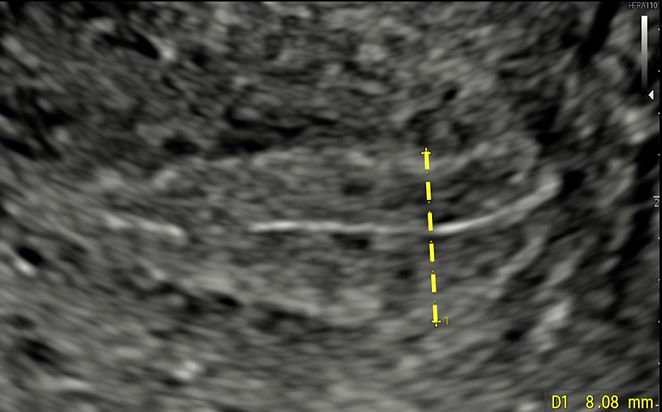

In a longitudinal plane of the uterus, the endometrium should be measured at its thickest point, including both endometrial layers. The measurement should be taken perpendicular to the midline, which corresponds to the line of junction between the two endometrial surfaces (Figure 4).

4

Longitudinal view of the uterus, showing measurement of the endometrium at its thickness point, perpendicular to the midline.